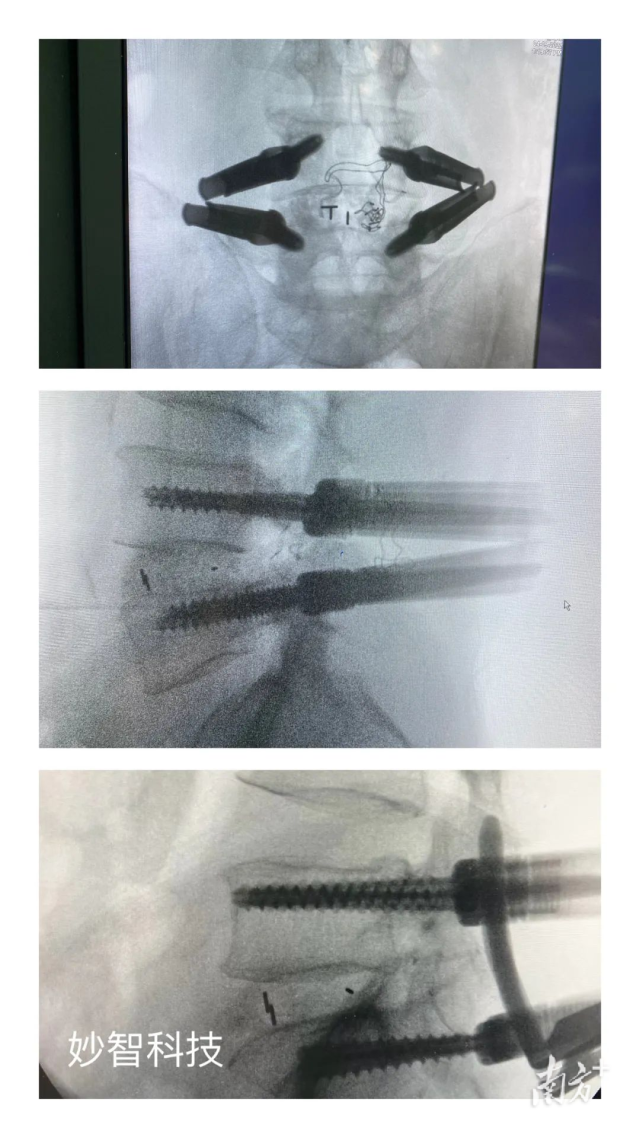

妙智科技研發(fā)的骨科機器人在臨床中試驗

由於新型醫(yī)療器械壹般研究周期較長,目前,妙智科技研發(fā)的骨科機器人仍在臨床試驗階段。截至2022年底,妙智科技已經完成了近50例臨床病例,預計今年計劃將完成取證並開始售賣。

其中,MVROT脊柱外科手術導航系統(tǒng)(手術機器人)作為妙智科技在研的壹種智能手術治療產品,主要用於脊柱外科開放或經皮手術中,通過7自由度,ForceFeedBack機械臂來輔助臨床醫(yī)生完成手術器械或植入物的定位,支持術前CT-術中2DCArm影像配準,系統(tǒng)空間精度1.5mm,力學測量精度0.25N,工作範圍40cmX40cmX40cm,為市場領先指標。該產品目標是使復雜的手術簡單化、精準化、可視化,安全度高、易操作,醫(yī)生學習曲線短,提高手術效率,大幅降低醫(yī)生和患者X線輻射量,大幅減少病人看病成本。